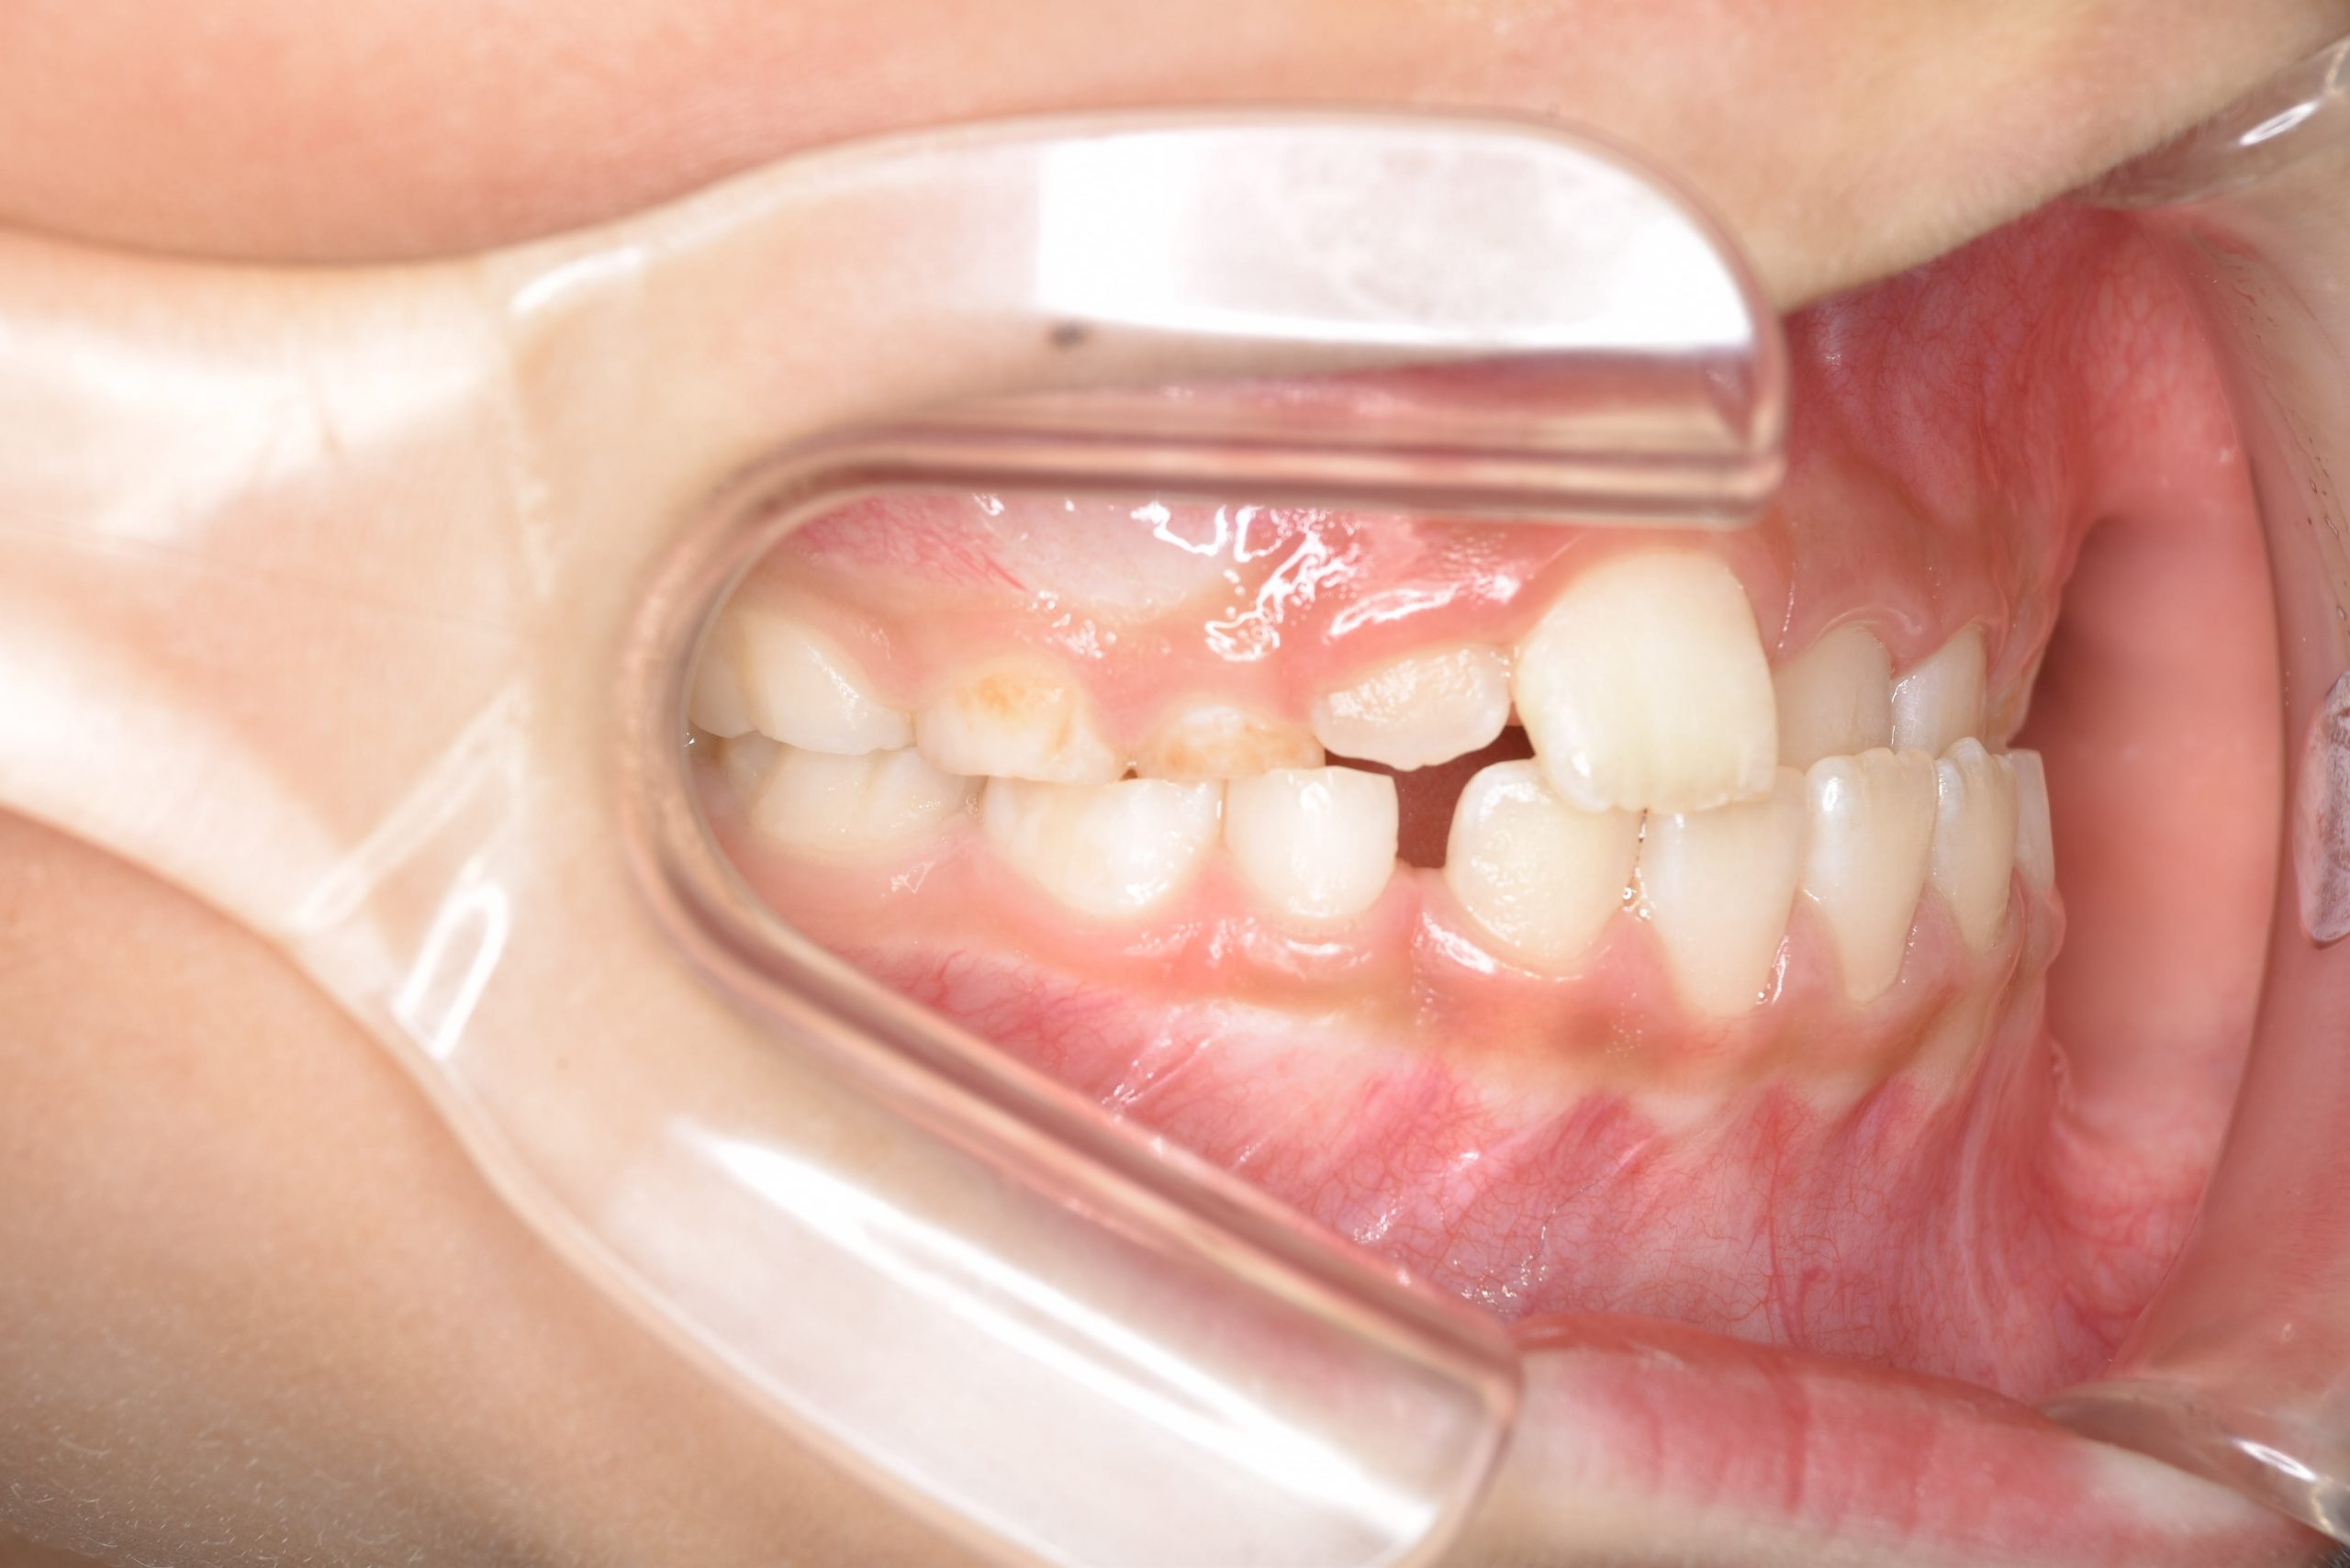

ビフォー

全顎ワイヤー矯正 症例_108

主訴 受け口|前歯がかみ合わない|顔貌

施術内容 小児矯正1期治療

治癒期間 3年11ヶ月間

費用 498,960円(税込)